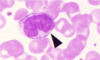

Basophil